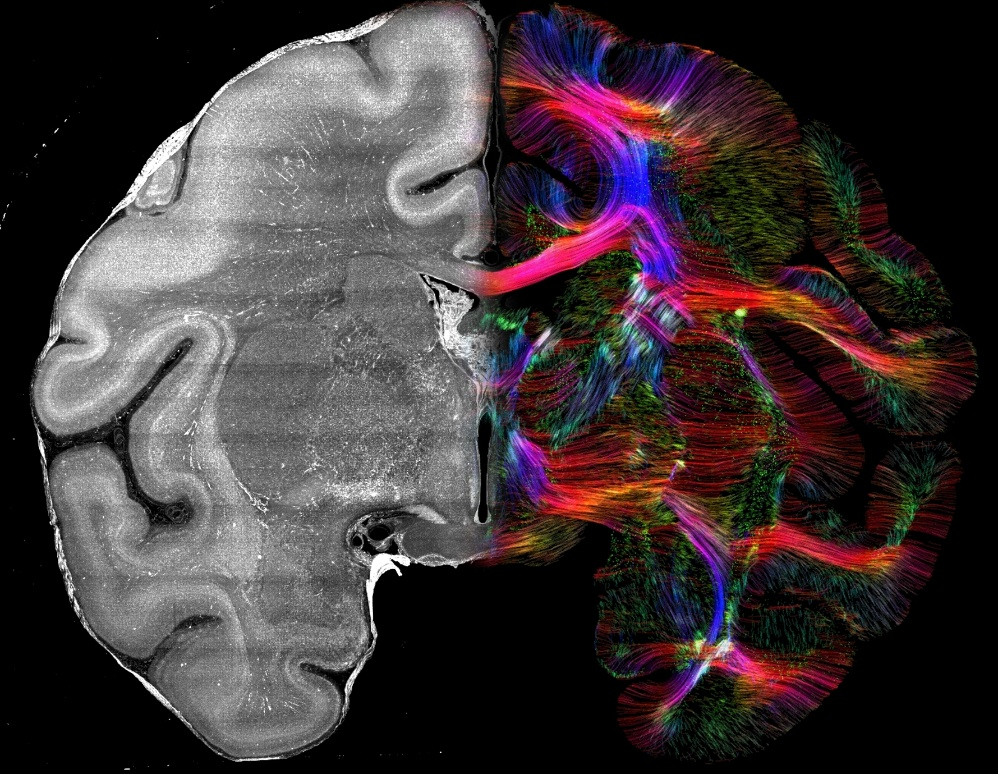

左侧是尼氏染色的猕猴脑切片,右侧是尼氏染色经过CABLE计算得到的纤维图像。颜色编码表示不同方向:红色代表左右向,绿色代表前后向,蓝色代表上下向。

技术流程上,研究团队基于深圳理工大学生命健康学院副教授、深圳先进院副研究员徐放等此前发表的SMART图谱技术体系,先对全脑进行300微米厚片切割,经过透明化和DAPI/Nissl染色后,再通过VISoR成像获取全脑三维数据,随后进行图像拼接和方向计算,最终实现纤维追踪。

结果显示,无论白质还是灰质区域,细胞排布都存在稳定指向性,与已知纤维方向高度一致,并且能够解析dMRI等技术中难以分辨的交叉纤维与弯折纤维。

纤维密集区域的放大图显示,细胞核(DAPI,绿色)在组织内呈条索状排布,其主方向与邻近轴突(白色)的走向基本一致。